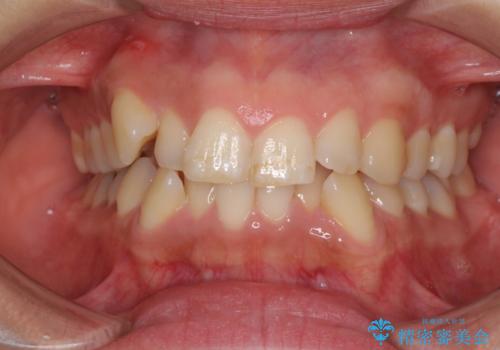

- 上下前歯のデコボコを気にして来院された患者様です。

デコボコが強いため、非抜歯で矯正をすると出っ歯仕上がりとなるため、上下左右の第一小臼歯4本を抜歯することとしました。